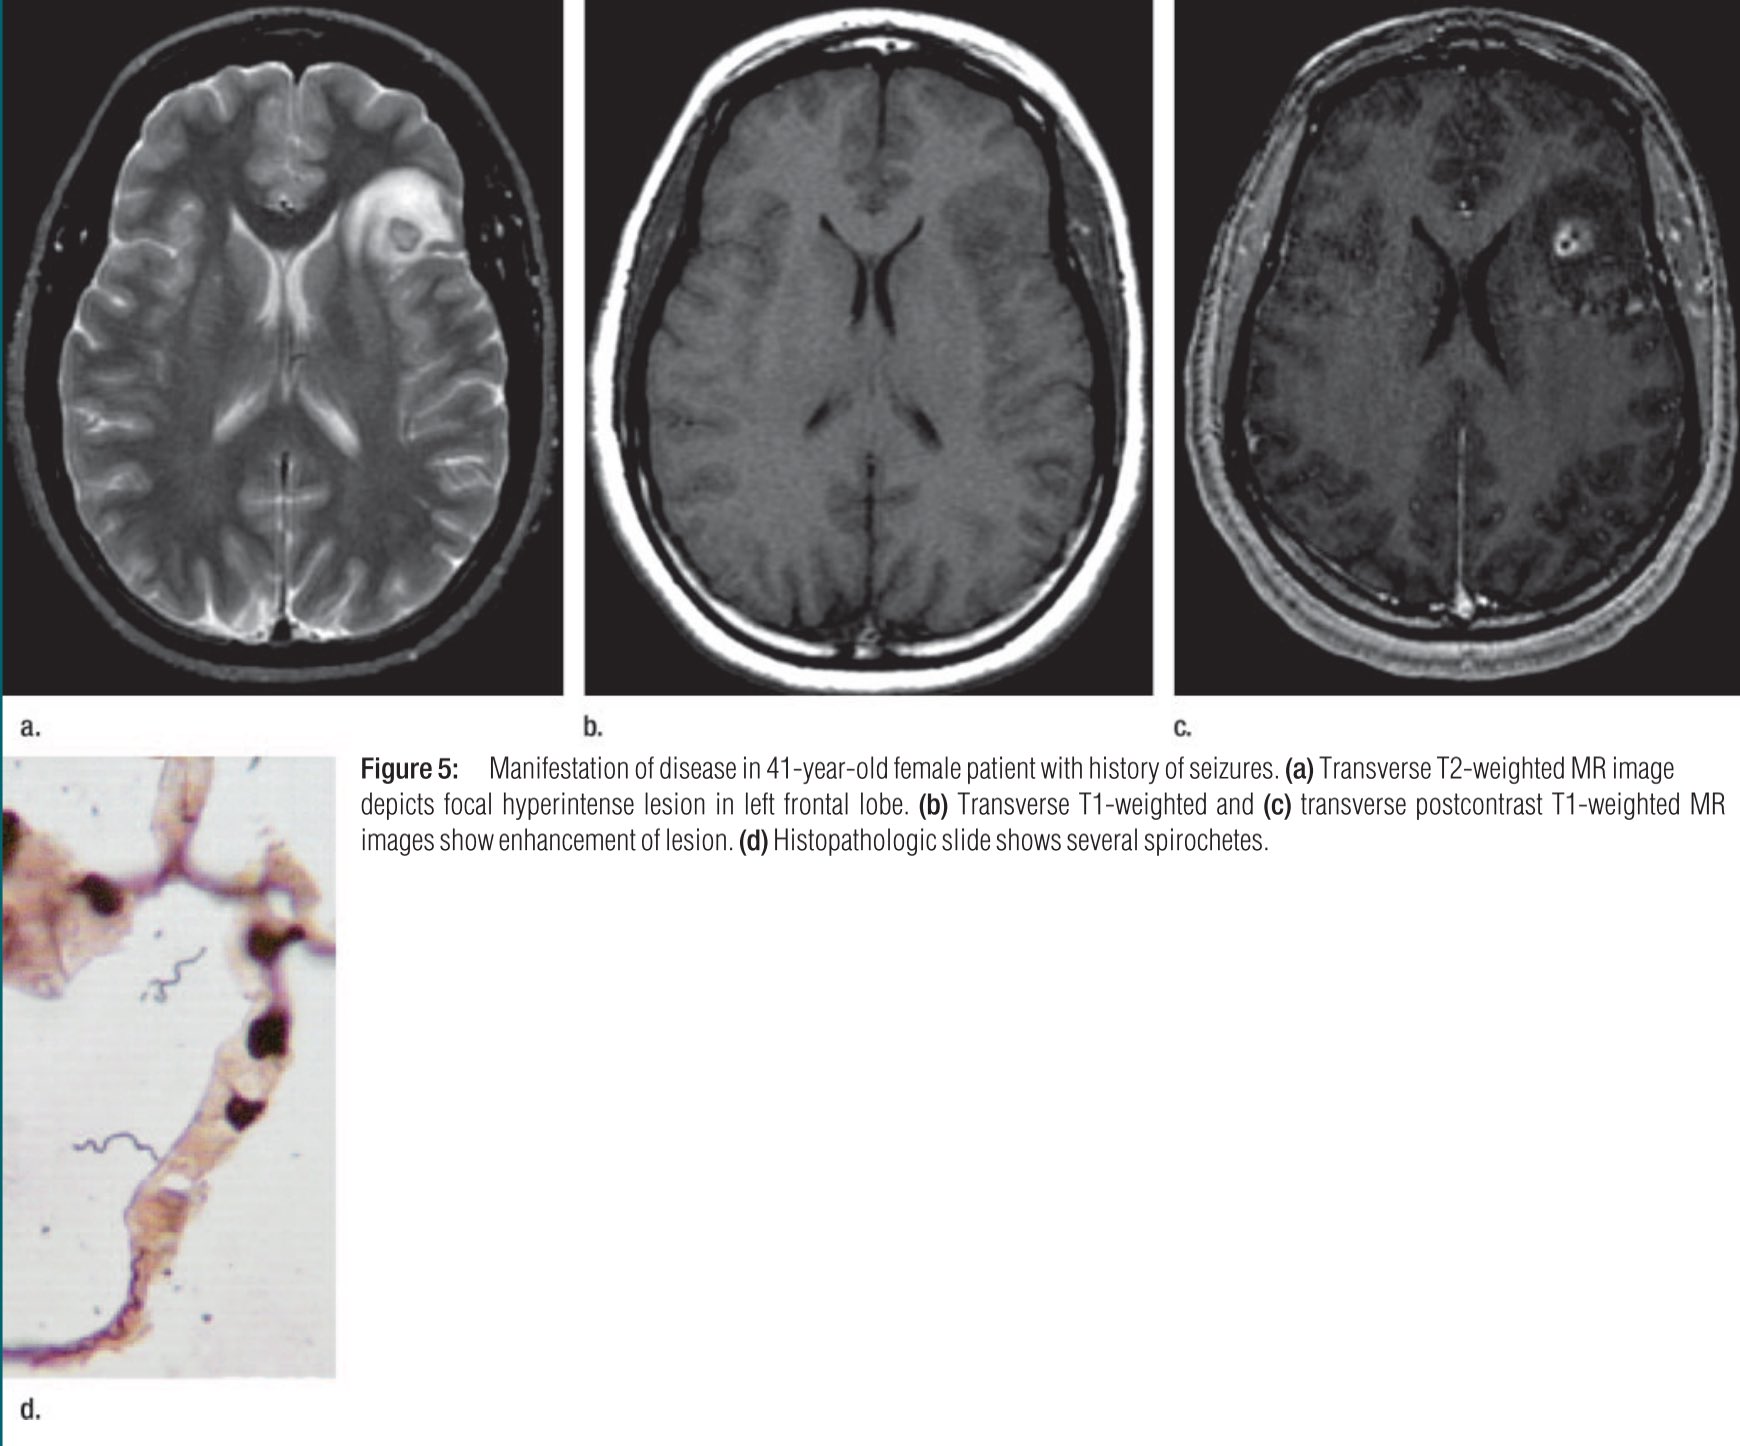

Figure 5 From Neuro Lyme Disease Mr Imaging Findings Semantic Scholar